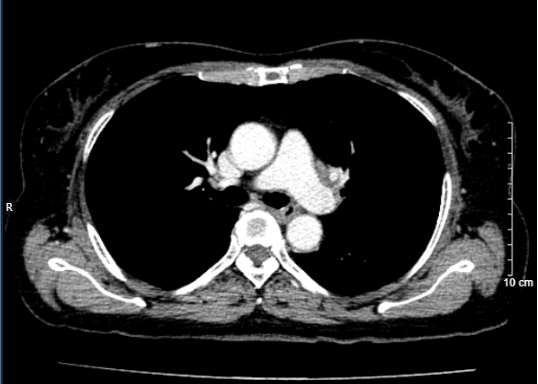

• Hình ảnh chụp cắt lớp vi tính lồng ngực sau 3 chu kì điều trị: Không thấy tổn thương khu trú hoặc lan tỏa nhu mô hai phổi. Không có hạch trung thất.

Hình 2: Hình ảnh trước điều trị (bên trái): Hình ảnh khối u và tổn thương di căn phổi cùng bên (mũi tên đỏ). Hình ảnh sau điều trị (bên phải): không còn khối u sau 3 chu kì điều trị

Hình 3: Hình bên trái (trước điều trị): Hình ảnh khối u (mũi tên vàng). Hình bên phải (sau điều trị): không còn tổn thương di căn phổi cùng bên sau 3 chu kì điều trị